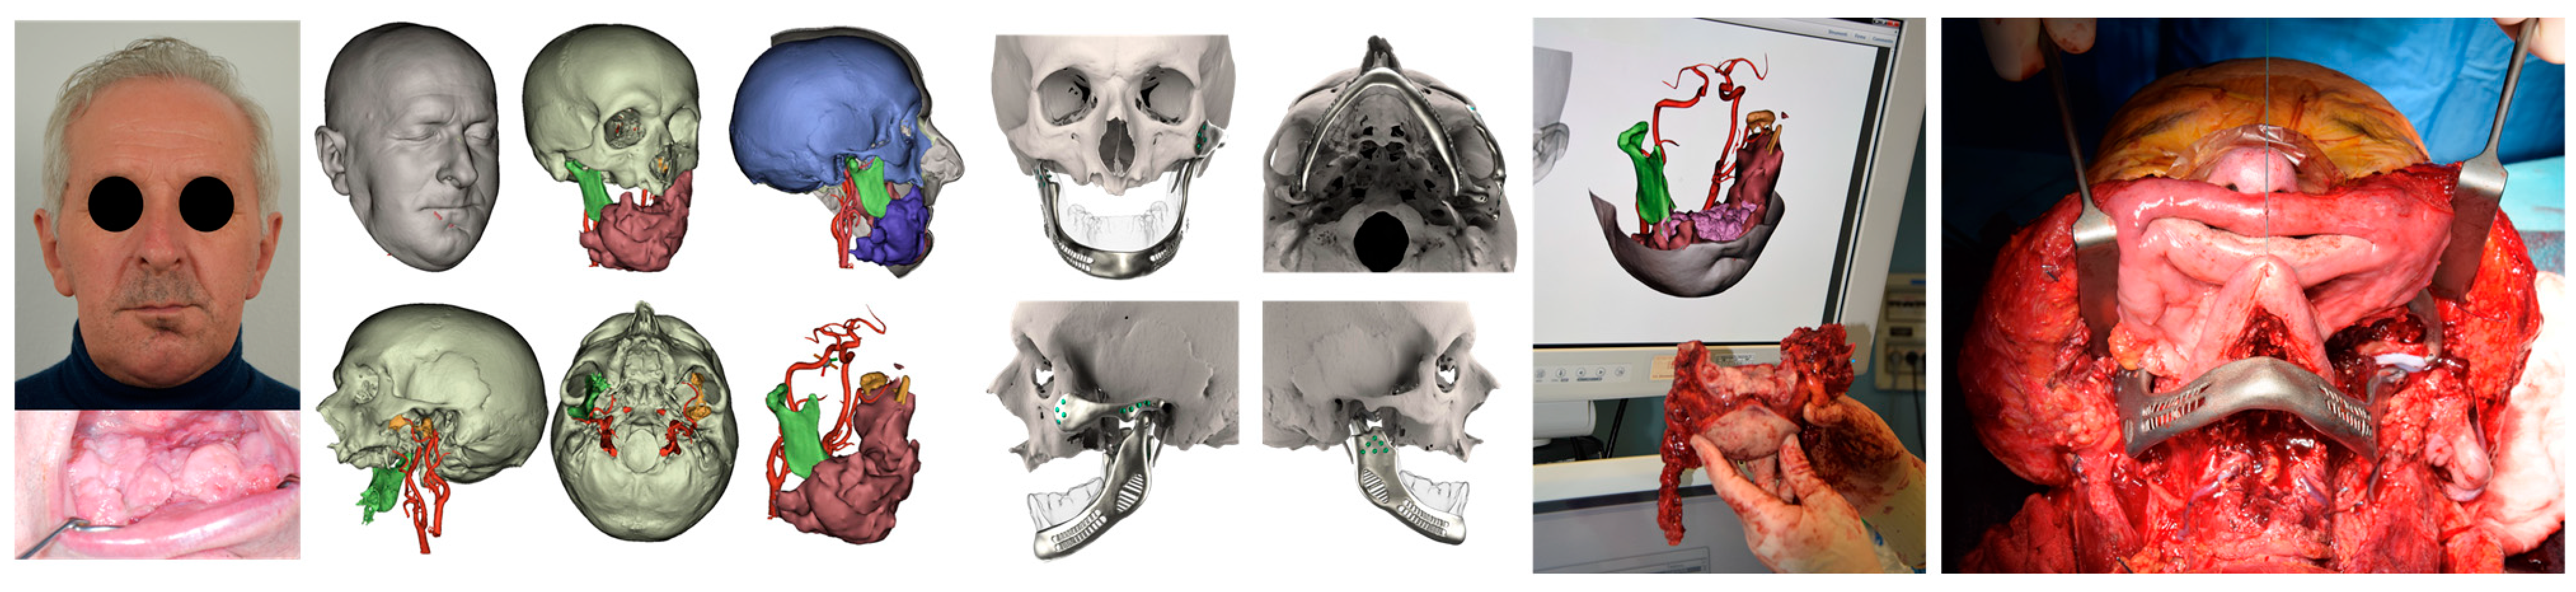

| ID | Age | eTMJR Class | Image | Reconstructed Structures | Fossa Materials | Condyle Materials | Screws and Fixation Holes |

|---|---|---|---|---|---|---|---|

| 1 | 71 | FT-M0 | ![]() | Temporal bone, aygomatic arch, glenoid fossa and condyle | Unalloyed titanium mesh temporal and zygomatic backing capping the UHMWPE fossa | Cobalt-chromiun-molybdenum alloy condylar head and Titanium alloy body | Skull component: 62.0 mm titanium screws. Manibular component: 82.7 mm titanium screws |

| 2 | 58 | FA-M0 | ![]() | Glenoid fossa with medial extension and condyle | Alloyed titanium backing capping the UHMWPE fossa | Cobalt-chromiun-molybdenum alloy condylar head and Titanium alloy body | Skull component: 52.0 mm titanium screws. Manibular component: 82.7 mm titanium screws |

| 3 | 41 | FO-M3 * | ![]() | Glenoid fossa and complete left hemimandible | Alloyed titanium backing capping the UHMWPE fossa | Cobalt-chromiun-molybdenum alloy condylar head and Titanium alloy body consisting of two interloching pieces | Skull component: 52.0 mm titanium screws. Manibular component: 112.7 mm titanium screws |

| 4 | 71 | FA-M3 | ![]() | Left zygomatic arch, glenoid fossa and complete left hemimandible extended to the right hemimandible ramus | Alloyed titanium zygomatic backing capping the UHMWPE fossa | Titantium alloy | Skull component: 82.3 mm titanium screws. Manibular component: 62.7 mm titanium screws |

| 5 | 26 | FA-M0 | ![]() | Temporal bone, zygomatic arch, glenoid fossa and condyle bilatreally | Alloyed titanium zygomatic backing capping the UHMWPE fossa | Cobalt-chromiun-molybdenum alloy condylar head and Titanium alloy body | Skull component: 172.0 mm titanium screws. Manibular component: 192.7 mm titanium screws |

| 6 | 54 | F0-M2 | ![]() | Glenoid fossa and complete right hemimandible | Alloyed titanium backing capping the UHMWPE fossa | Cobalt-chromiun-molybdenum alloy condylar head and Titanium alloy mesh body | Skull component: 52.3 mm titanium screws. Manibular component: 92.7 mm titanium screws |

| 7 | 63 | F0-M3 | ![]() | Glenoid fossa and complete left hemimandible | Alloyed titanium backing capping the UHMWPE fossa | Cobalt-chromiun-molybdenum alloy | Skull component: 52.3 mm titanium screws. Manibular component: 82.7 mm titanium screws |

| 8 | 24 | F0-M3 * | ![]() | Glenoid fossa and complete right hemimandible extended to the left hemimandible ramus | Cobalt-chromium-molybdenum alloy backing capping the UHMWPE fossa | Cobalt-chromiun-molybdenum alloy | Skull component: 52.3 mm titanium screws. Manibular component: 112.7 mm titanium screws |

| 9 | 52 | FT-M0 | ![]() | Temporal bone, zygomatic arch, glenoid fossa extended medially and condyle | Cobalt-chromium-molybdenum alloy backing capping the UHMWPE fossa | Cobalt-chromiun-molybdenum alloy | Skull component: 82.3 mm titanium screws. Manibular component: 82.7 mm titanium screws |

| ID | Age | Gender | Diagnosis | Complications | eTMJR Class | MIO before Surgery | MIO after Surgery | VAS Preoperatory | VAS at 6 Months | Follow-Up |

|---|---|---|---|---|---|---|---|---|---|---|

| 1 | 71 | Female | Ossifying fibroma o right temporal bone | None | FT-M0 | 29 mm | 35 mm | 2 | 0 | 5 years |

| 2 | 58 | Male | Left condylar osteoma | Partial left facial palsy | FA-M0 | 20 mm | 32 mm | 7 | 2 | 5 years |

| 3 | 41 | Male | Sarcomatoid carcinoma of lef hemimandible | None | F0-M3 * | 35 mm | 35 mm | 4 | 3 | 1 year |

| 4 | 71 | Male | High grade Mucoepidermoid carcinoma of the oral pelvis | Periprocedural pulmonary infection, Partial left facial palsy | FA-M3 | 27 mm | 30 mm | 7 | 5 | 4 years |

| 5 | 26 | Male | Bilateral severe TMJ ankylosis | None | FA-M0 | 8 mm | 24 mm | 8 | 1 | 4 years |

| 6 | 54 | Female | Left mandibular angle odontogenic keratocyst | None | F0-M2 | 36 mm | 38 mm | 5 | 3 | 3 years |

| 7 | 63 | Female | Infiltrating squamous cell carcinoma of the left cheek mucosa | Loss of the implant | F0-M3 | 23 mm | 34 mm | 5 | 2 | 2 years |

| 8 | 24 | Male | Right hemifacial fibrous dysplasia | None | F0-M3 * | 24 mm | 31 mm | 3 | 0 | 1 year |

| 9 | 52 | Female | Left articular eminence osteoblastoma | None | FT-M0 | 10 mm | 33 mm | 7 | 1 | 8 months |